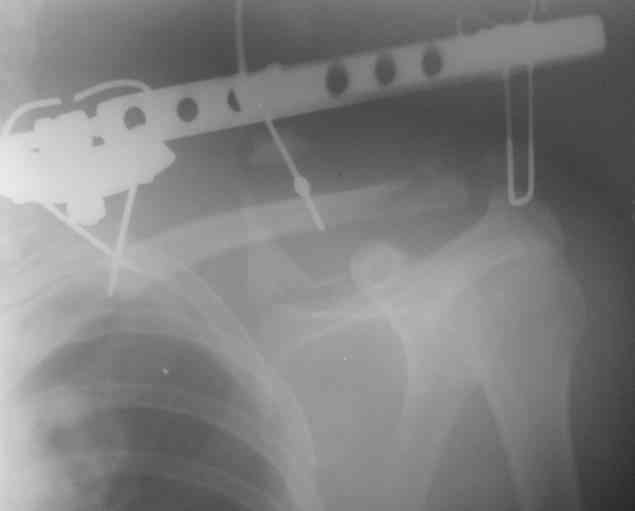

Перелом угла лопатки

На снимке перелом угла лопатки. Довольно крупный размер осколка.

Следует ли оперировать такой перелом? Если есть резон оперативного лечения, то каким образом? (рекон. пластина, закрыто пришпилить спицами, винтами). ЭОПа в наличии нет.

В области лопатки массивный отек мягких тканей.